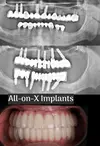

علاج الزرعات السنية